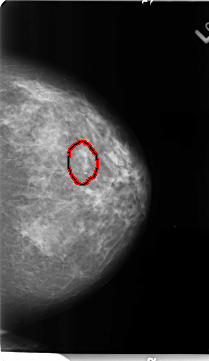

B_3125_1.LEFT_CC

LEFT_CC LINES 4688 PIXELS_PER_LINE 2712 BITS_PER_PIXEL 12 RESOLUTION 50 OVERLAY

FILE: B_3125_1.LEFT_CC.OVERLAY

TOTAL_ABNORMALITIES 1

ABNORMALITY 1

LESION_TYPE CALCIFICATION TYPE PUNCTATE DISTRIBUTION CLUSTERED

ASSESSMENT 3

SUBTLETY 2

PATHOLOGY BENIGN

TOTAL_OUTLINES 1

BOUNDARY